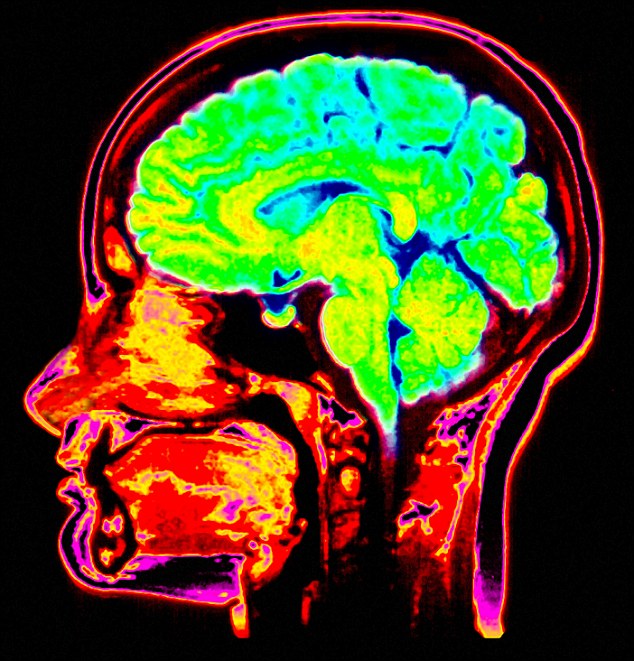

The scientists monitored the dreamers with both magnetic resonance imaging and near-infrared spectroscopy to see patterns of heat in their subject’s heads, which gives a picture of brain activity.